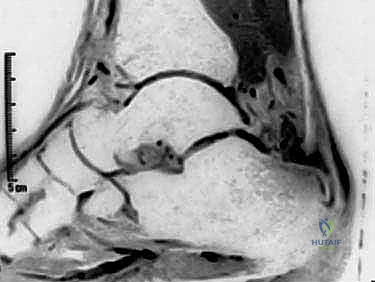

- التصوير بالرنين المغناطيسي (MRI): هو المعيار الذهبي والأداة الأقوى. يوفر صوراً ثلاثية الأبعاد وعالية الدقة تُظهر بدقة حجم التلف داخل الوتر، الأنسجة الندبية، حالة الجراب الزلالي، ومدى صلاحية وتر (FHL) لاستخدامه في الجراحة.

يتم استبدال الكولاجين القوي من النوع الأول (Type I Collagen) بكولاجين أضعف من النوع الثالث (Type III Collagen). تزداد سماكة الوتر وتتكون أوعية دموية جديدة هشة وأعصاب صغيرة تتغلغل في نسيج الوتر، وهي المسؤولة عن الألم المزمن. مع مرور الوقت، وتحديداً عند نقطة الاتصال بالعظم، تبدأ الأنسجة التالفة في التكلس (تتحول إلى نسيج عظمي داخل الوتر)، مما يفقده مرونته تماماً ويجعله قاسياً ومؤلماً وعرضة للتمزق الكامل في أي لحظة.

هذه الحالة تختلف جذرياً عن الالتهاب الحاد (Tendinitis). فالاعتلال (Tendinosis) هو عملية مزمنة تتميز بتدهور الأنسجة الكولاجينية المكونة للوتر، وتراكم الأنسجة الندبية الضعيفة، وتكون التكلسات العظمية، مما يؤدي إلى ضعف بنيوي في الوتر يجعله عرضة للتمزق، مصحوباً بألم مستمر لا يطاق.